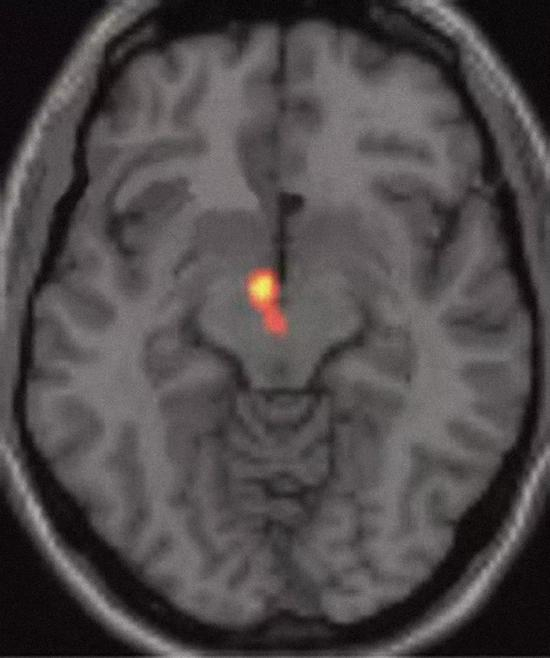

亲吻多少和爱关联,因此会增加大脑中控制快乐和狂喜的化学物质,并激发与人交往的愿望。2005年,美国罗格斯大学(Rutgers University)的人类学家海伦·费希尔(Helen Fisher)和同事报道了一项研究。他们让17个受试者凝视自己深爱的人的相片,并对他们的大脑进行扫描。研究者在控制快乐、动机和奖赏的两个区域,即右腹侧被盖区(right ventral tegmental area)和右侧尾状核(right caudate nucleus),发现大脑活动激增(参见下图)。可卡因之类的成瘾药物也会释放神经递质多巴胺,刺激大脑的奖赏中枢。这样看来,爱情还真是一剂不折不扣的“迷魂药”。

研究显示,看着自己深爱的人时,大脑的腹侧被盖区会被激活,成瘾药物同样会激活这个快乐中枢。如果亲吻和爱有关,那么它简直无异于一剂大脑“麻醉药”。